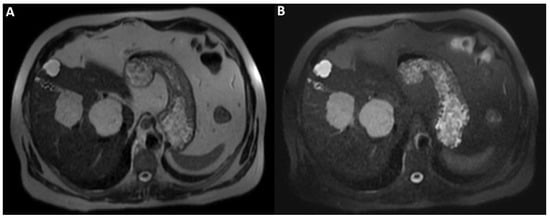

A man in his early 60s with unremarkable medical history and normal laboratory data underwent an abdominal ultrasound for insurance reasons, which detected two liver lesions, the largest one localized deeply in the hepatic parenchyma. Due to the patient’s high body mass index, which reduced the ultrasound’s diagnostic quality, panoramic imaging was required to achieve the final diagnosis. Therefore, the patient underwent liver Magnetic Resonance Imaging (MRI) performed with hepatospecific contrast agent (Gd-EOB-DTPA). MRI was performed by using a 1.5 T superconducting system (Signa; GE Medical Systems, Milwaukee, Brookfield, WI, USA) with a body phased-array multicoil for signal detection. The two liver lesions appeared to be inhomogeneously hyperintense on T2-Weighted Images (T2WI) (straight arrow and arrowhead in (A)) and on Diffusion-Weighted Images with b-value = 800 (DWI) (straight arrow and arrowhead in (B)) and homogeneously hypointense on T1-Weighted Images (T1WI) (straight arrow and arrowhead in (C), in-phase T1WI, and (D) opposed-phase T1WI). It was not possible to establish the benignity of the two liver lesions evaluating T2WI and DWI acquired after contrast agent administration, in particular due to the inhomogeneous signal intensity shown on T2WI. To ascertain that it had not been caused by the contrast-induced reduction in the hydrogen nuclei relaxation time, it was necessary to re-acquire the same images without previous contrast administration a few days later.